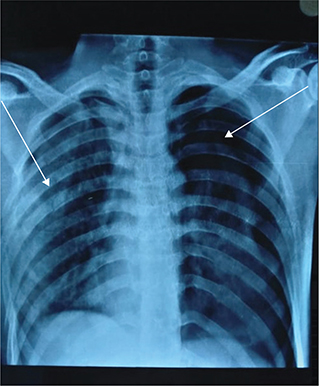

Chest X-ray (Figure 3) revealed bilateral pneumothorax primarily on the left, with a mediastinal shift towards the right side. A fracture of the right second and third ribs and a segmental fracture of the right 4th to 8th ribs were suggestive of a flail chest. Gross pneumothorax of the left lung resulted in a partial collapse of the left lung. High-resolution computed tomography (HRCT) of the chest revealed extensive right and minor left pneumothorax, bilateral lung contusions, a right clavicle medial end fracture, and multiple rib fractures.

Fig. 3. Chest X-ray of the patient revealed pneumothorax (right arrow) and rib fractures (left arrow).